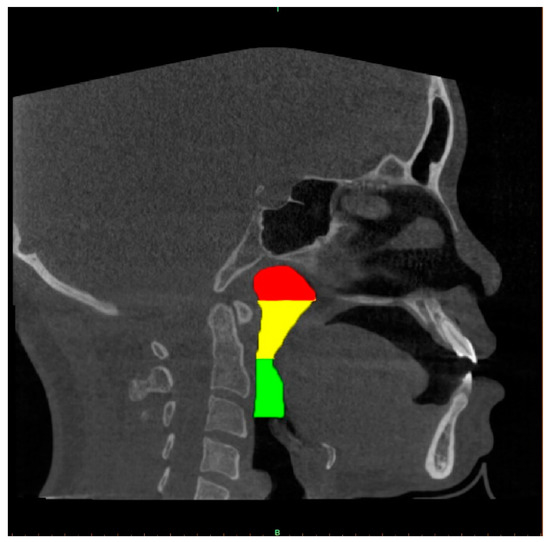

2.4. Upper Airway Segmentation

2.4.1. Manual Segmentation of the Airway and Data Augmentation

2.4.2. AI Segmentation Models